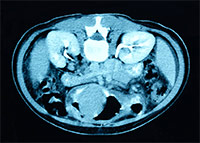

NEOPLASMS OF KIDNEY (RENAL CELL CARCINOMA) RENAL PELVIS ...

Kidney cancer is a type of cancer that starts in the cells in the kidney. The two most common types of kidney cancer are renal cell carcinoma (RCC) and treatments. If the cancer has not spread, it usually will be removed by surgery. Sometimes this ... View Full Source